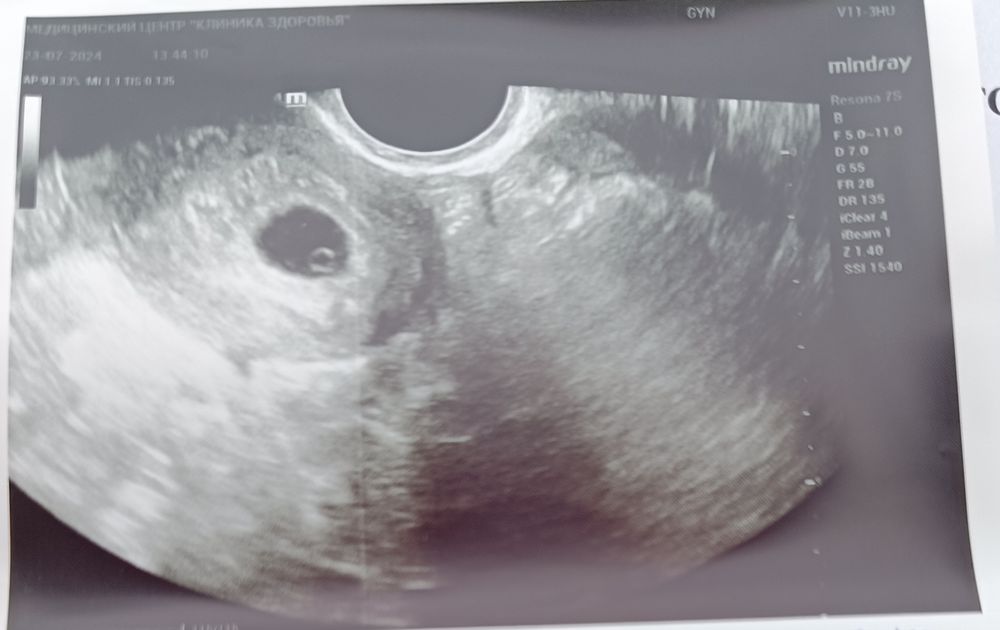

Первое УЗИ

Кто разбирает, подскажите 😂 УЗИ 7 недель